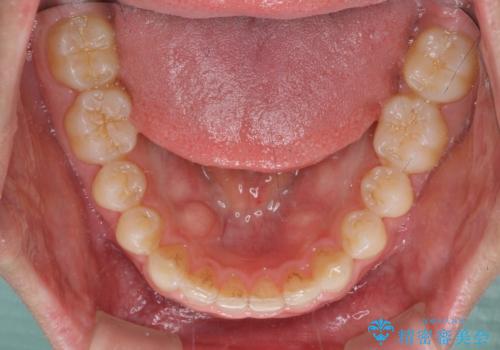

- 上下の前歯の隙間を気にして来院された患者様です。

インビザラインを用い、上下歯列のスペースを閉じていくこととしました。

銀行にお勤めのため、突然の転勤により通院が大変な状況となりましたが、インビザラインであれば2-3ヶ月に1度を目安に来院いただき、無事に治療を終えることができました。